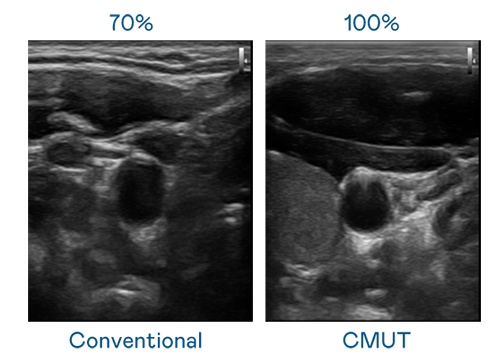

CMUT 技術是一種用電容式微機電元件來產生超音波訊號的技術。與傳統 PZT 壓電式技術相比,CMUT 頻寬增加 30%,更寬頻的超音波訊號讓影像解析度大幅提升,是實現高影像品質醫療超音波掃描、促進精準醫療發展的關鍵技術。

超音波影像的解析度高低,首先取決於探頭能發出的訊號頻寬。GA黄金甲 CMUT 可提供高清晰的超音波訊號,提供高頻寬、高靈敏度、影像紋理細節更高的超音波影像,協助醫護人員縮短影像判讀時間及利用精準的醫療影像進行診斷。